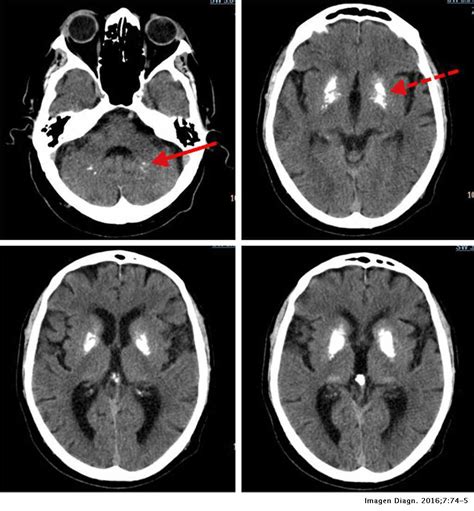

Enfermedad De Fahr | We did not find results for: Maybe you would like to learn more about one of these? Check spelling or type a new query. Primary familial brain calcification (pfbc), also known as familial idiopathic basal ganglia calcification (fibgc) and fahr's disease, is a rare, genetically dominant, inherited neurological disorder characterized by abnormal deposits of calcium in areas of the brain that control movement. Through the use of ct scans, calcifications are seen primarily in the basal ganglia and in other areas such a.

Through the use of ct scans, calcifications are seen primarily in the basal ganglia and in other areas such a. Maybe you would like to learn more about one of these? Primary familial brain calcification (pfbc), also known as familial idiopathic basal ganglia calcification (fibgc) and fahr's disease, is a rare, genetically dominant, inherited neurological disorder characterized by abnormal deposits of calcium in areas of the brain that control movement. We did not find results for: Check spelling or type a new query.